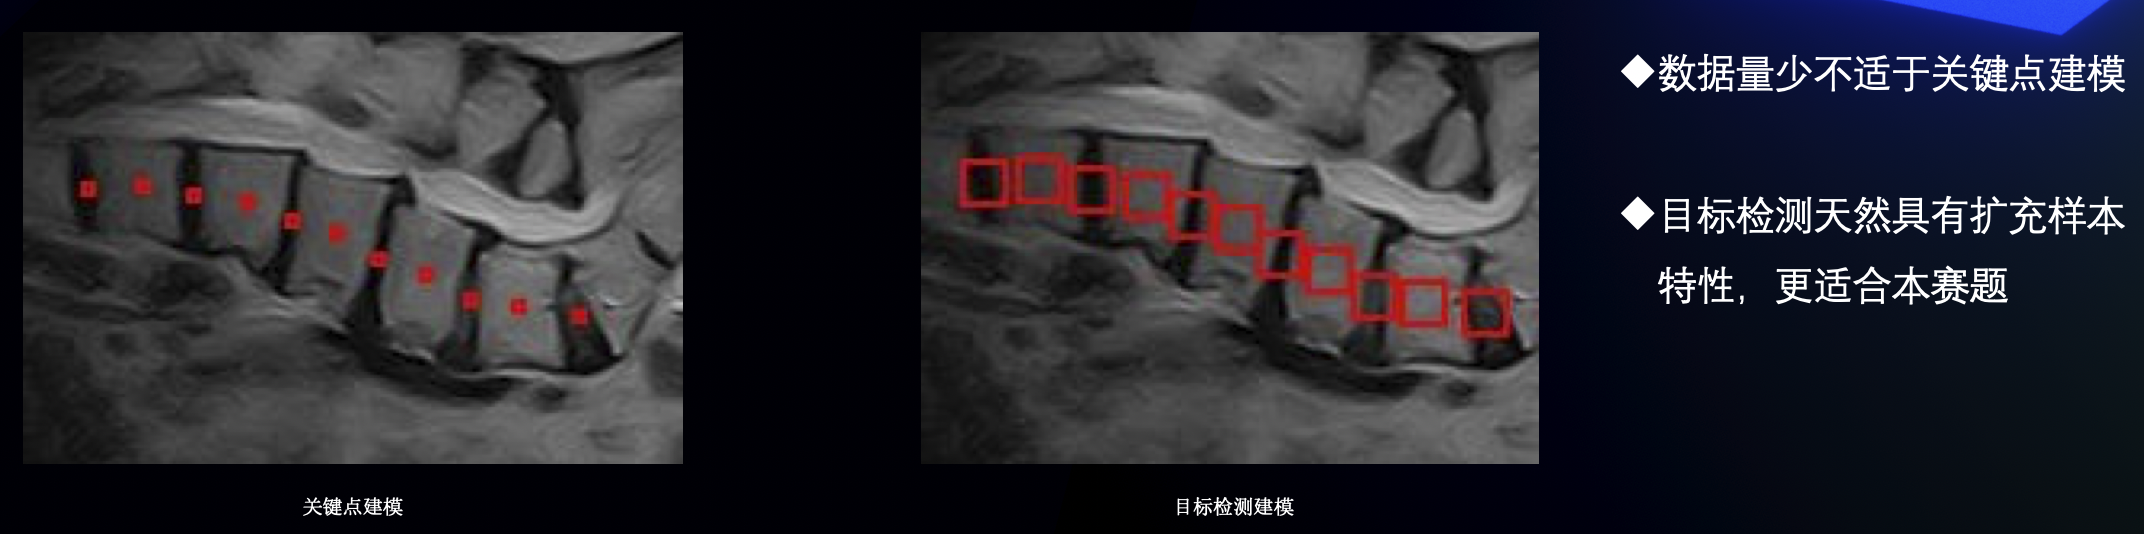

建模思路

我们队伍把本次比赛当成检测任务来做

算法部分

- 数据方面,我们把每个椎类点外扩做成gt框,最后用一个最小外界矩阵框住所有框。